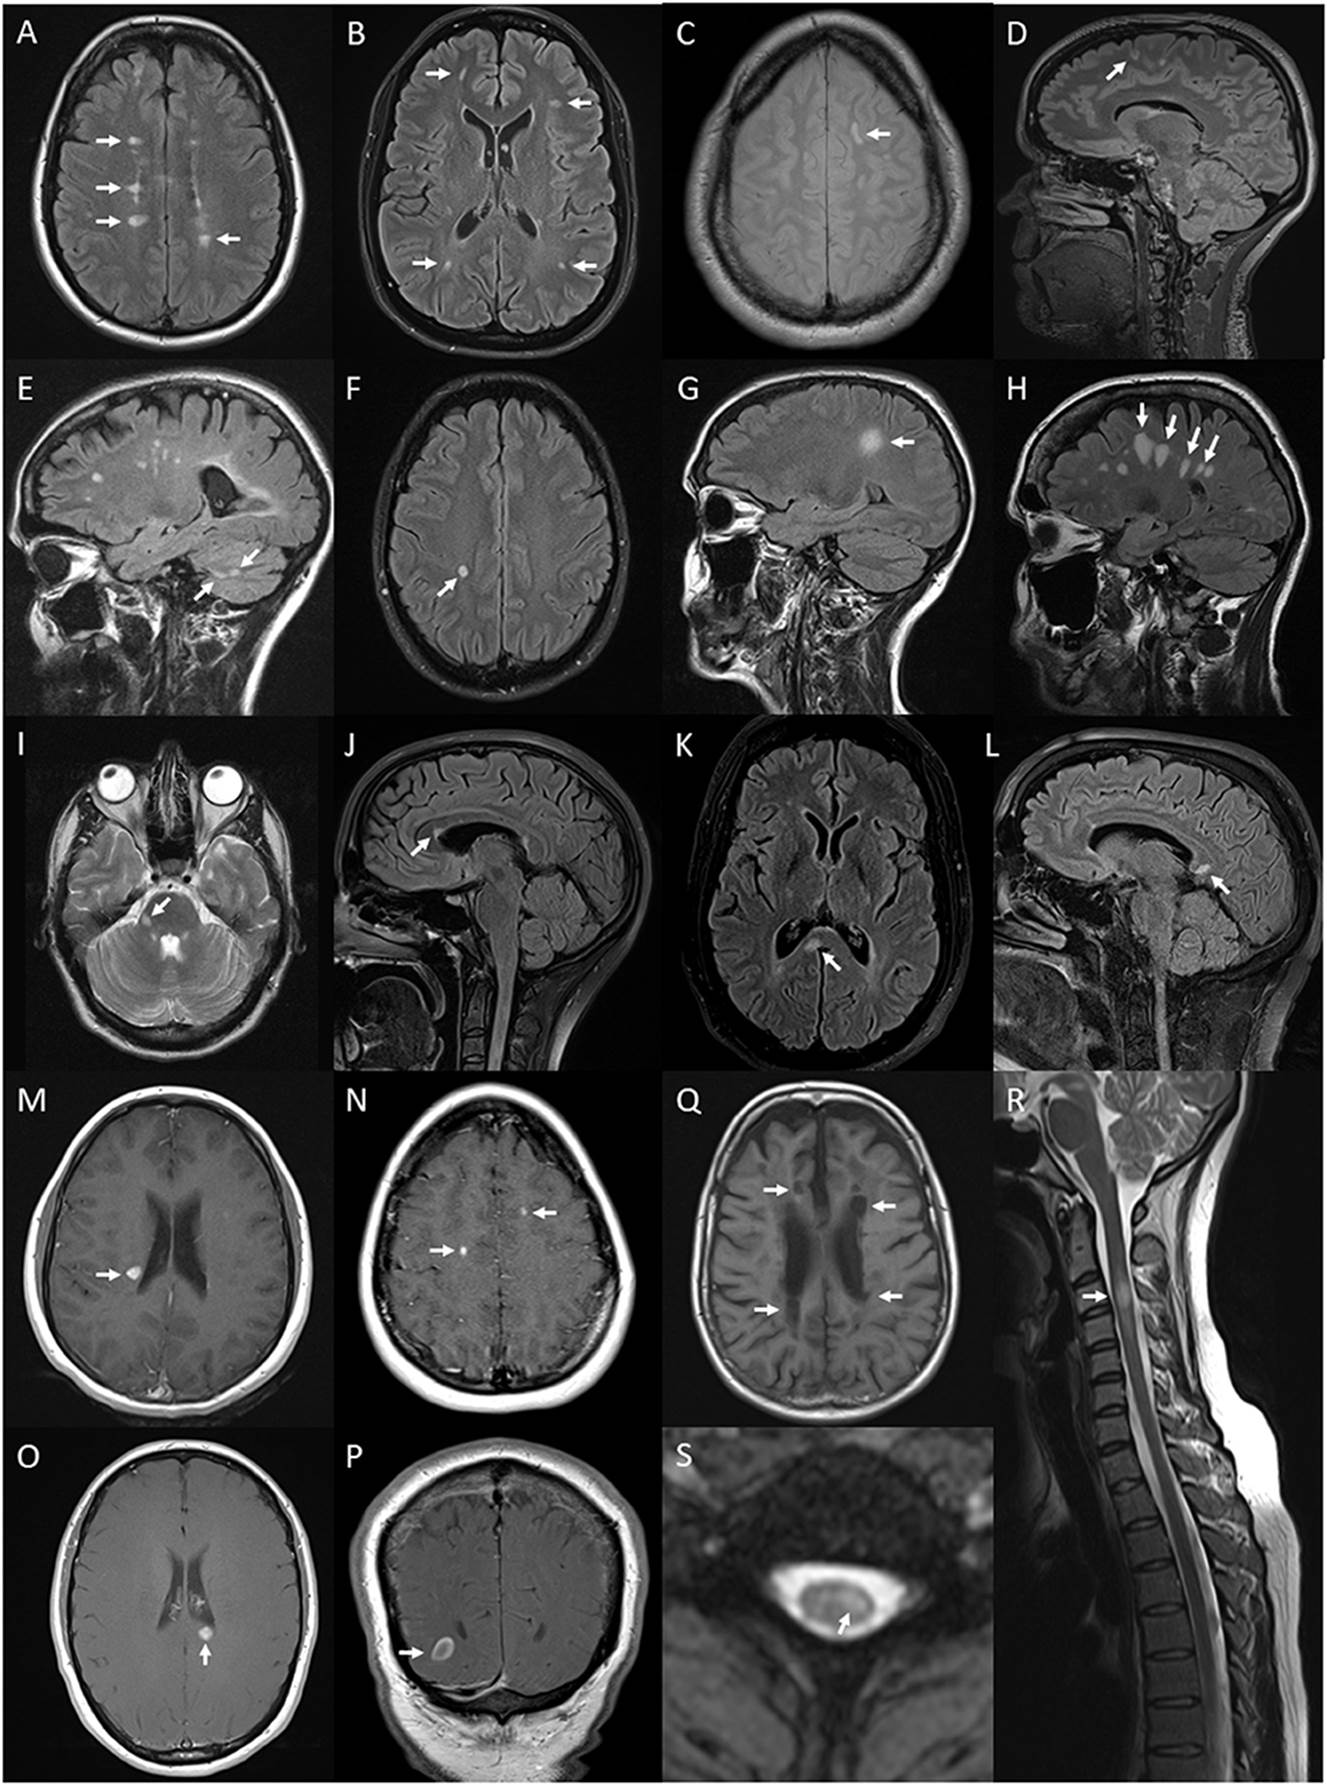

Below figures from: Clarke L, Arnett S, Broadley SA et al. MRI Patterns Distinguish AQP4 Antibody Positive Neuromyelitis Optica Spectrum Disorder From Multiple Sclerosis. Front Neurol. 2021 Sep 9;12:722237. doi:

Figure 6. Lesions and features on MRI of brain and spinal

cord associated with multiple sclerosis: periventricular hyperintense T2 white

matter lesions (arrows) on axial FLAIR image of the brain (A); subcortical T2 white matter lesions (arrows) on axial FLAIR

image of the brain (B); juxtacortical hyperintense T2 white matter lesion (arrow)

on axial proton density image of the brain (C); cortical hyperintense T2 lesion (arrow) on sagittal FLAIR

image of the brain (D); cerebellar hyperintense T2 lesions (arrows) on sagittal

FLAIR image of the brain (E); ovoid hyperintense T2 periventricular lesion (arrow) on

axial FLAIR image of the brain (F); large supratentorial T2 lesion (arrow) on sagittal FLAIR

image of the brain (G); Dawson's finger lesions (arrows) on sagittal FLAIR image of

the brain (H); right cerebellar peduncle hyperintense T2 lesion

(arrow) on axial T2 image of the brain (I); pyramidal corpus callosum hyperintense T2 lesion (arrow) on

sagittal FLAIR image of the brain (J); splenium hyperintense T2 lesion (arrow) on axial (K) and sagittal (L) FLAIR images of the brain; Gd-enhancing T1 lesions of

periventricular (arrow) (M), juxtacortical (arrows) (N), splenium (arrow) (O) regions on axial T1 images of the brain and

ring-enhancing lesion (arrow) on coronal T1 image of the brain (P); hypointense T1 (black hole) lesions (arrows) on axial T1

image of the brain (Q); short segment C3 T2 lesion (arrow) on sagittal T2 image of

the cervical spinal cord (R); and hyperintense T2 partial cord lesion (arrow) on axial T2

image of the cervical spinal cord (S).